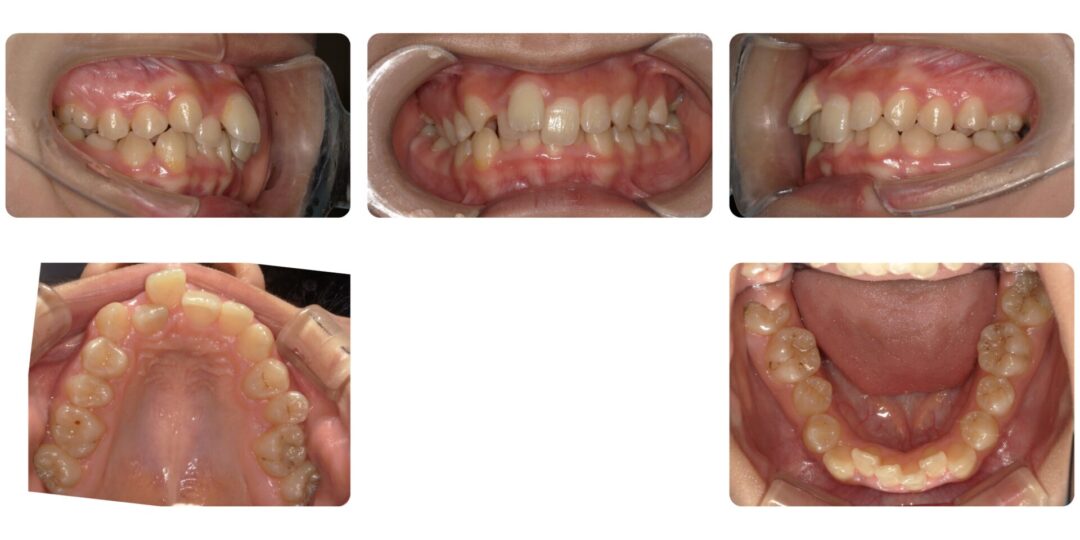

矯正治療前

過蓋咬合を伴う重度叢生|初診時15歳

上の前歯のガタガタが気になる

第二期治療 右上4番抜歯 マルチブラケット装置による歯列矯正